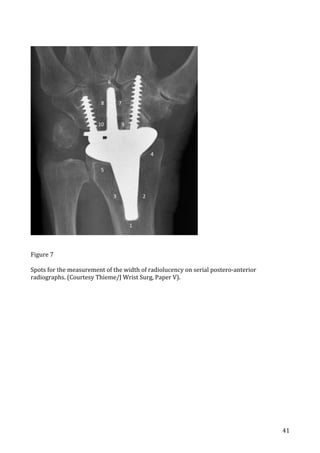

paper

V 15

, we (Guillaume Herzberg and myself) used the

measurement

software

provided

by

Sectra

(Sectra

AB,

Linköbing,

Sweden).

We

did

the

measurements

together

in

order

to

obtain

consensus

and

uniformity,

but

made

no

further

attempt

validate

measurements.

VI

16

,

were

done

independently

with

2

blinded

raters

(Lars

S.

Vadstrup

myself)

inter-­‐rater

reliability

assessed

on

a

total

of

820

width

radiolucent

zones.